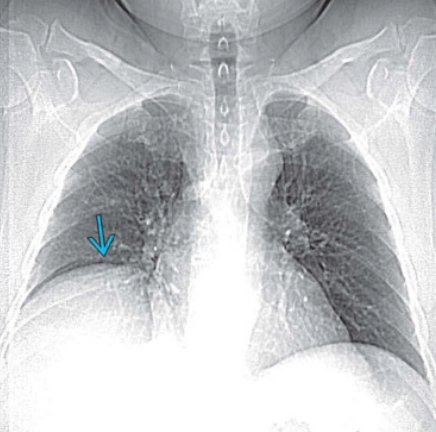

Nhão cơ hoành (ngực) - Diaphragmatic eventration (chest)

Liệt cơ hoành (Diaphragmatic Paralysis)(ngực)